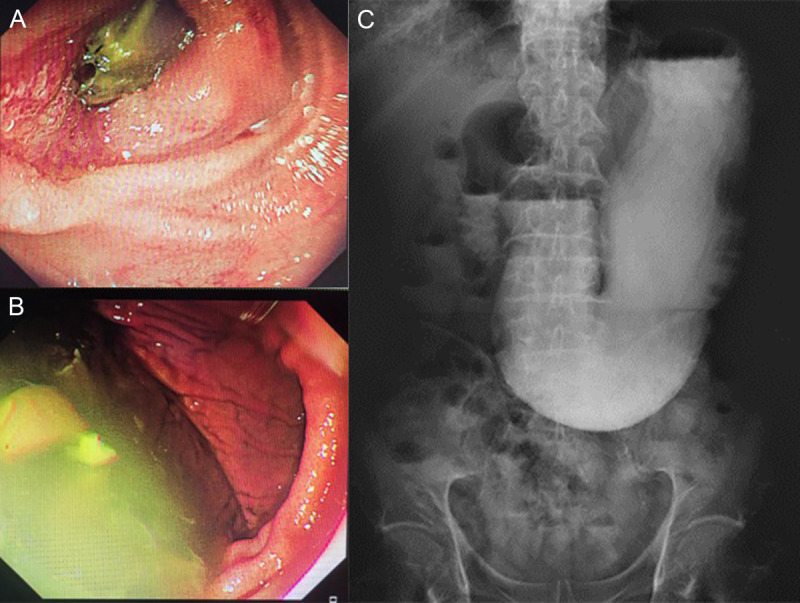

EUS-led breakthrough: An innovative journey to overcome complete gastric outlet obstruction by gastroenterostomy (with video).